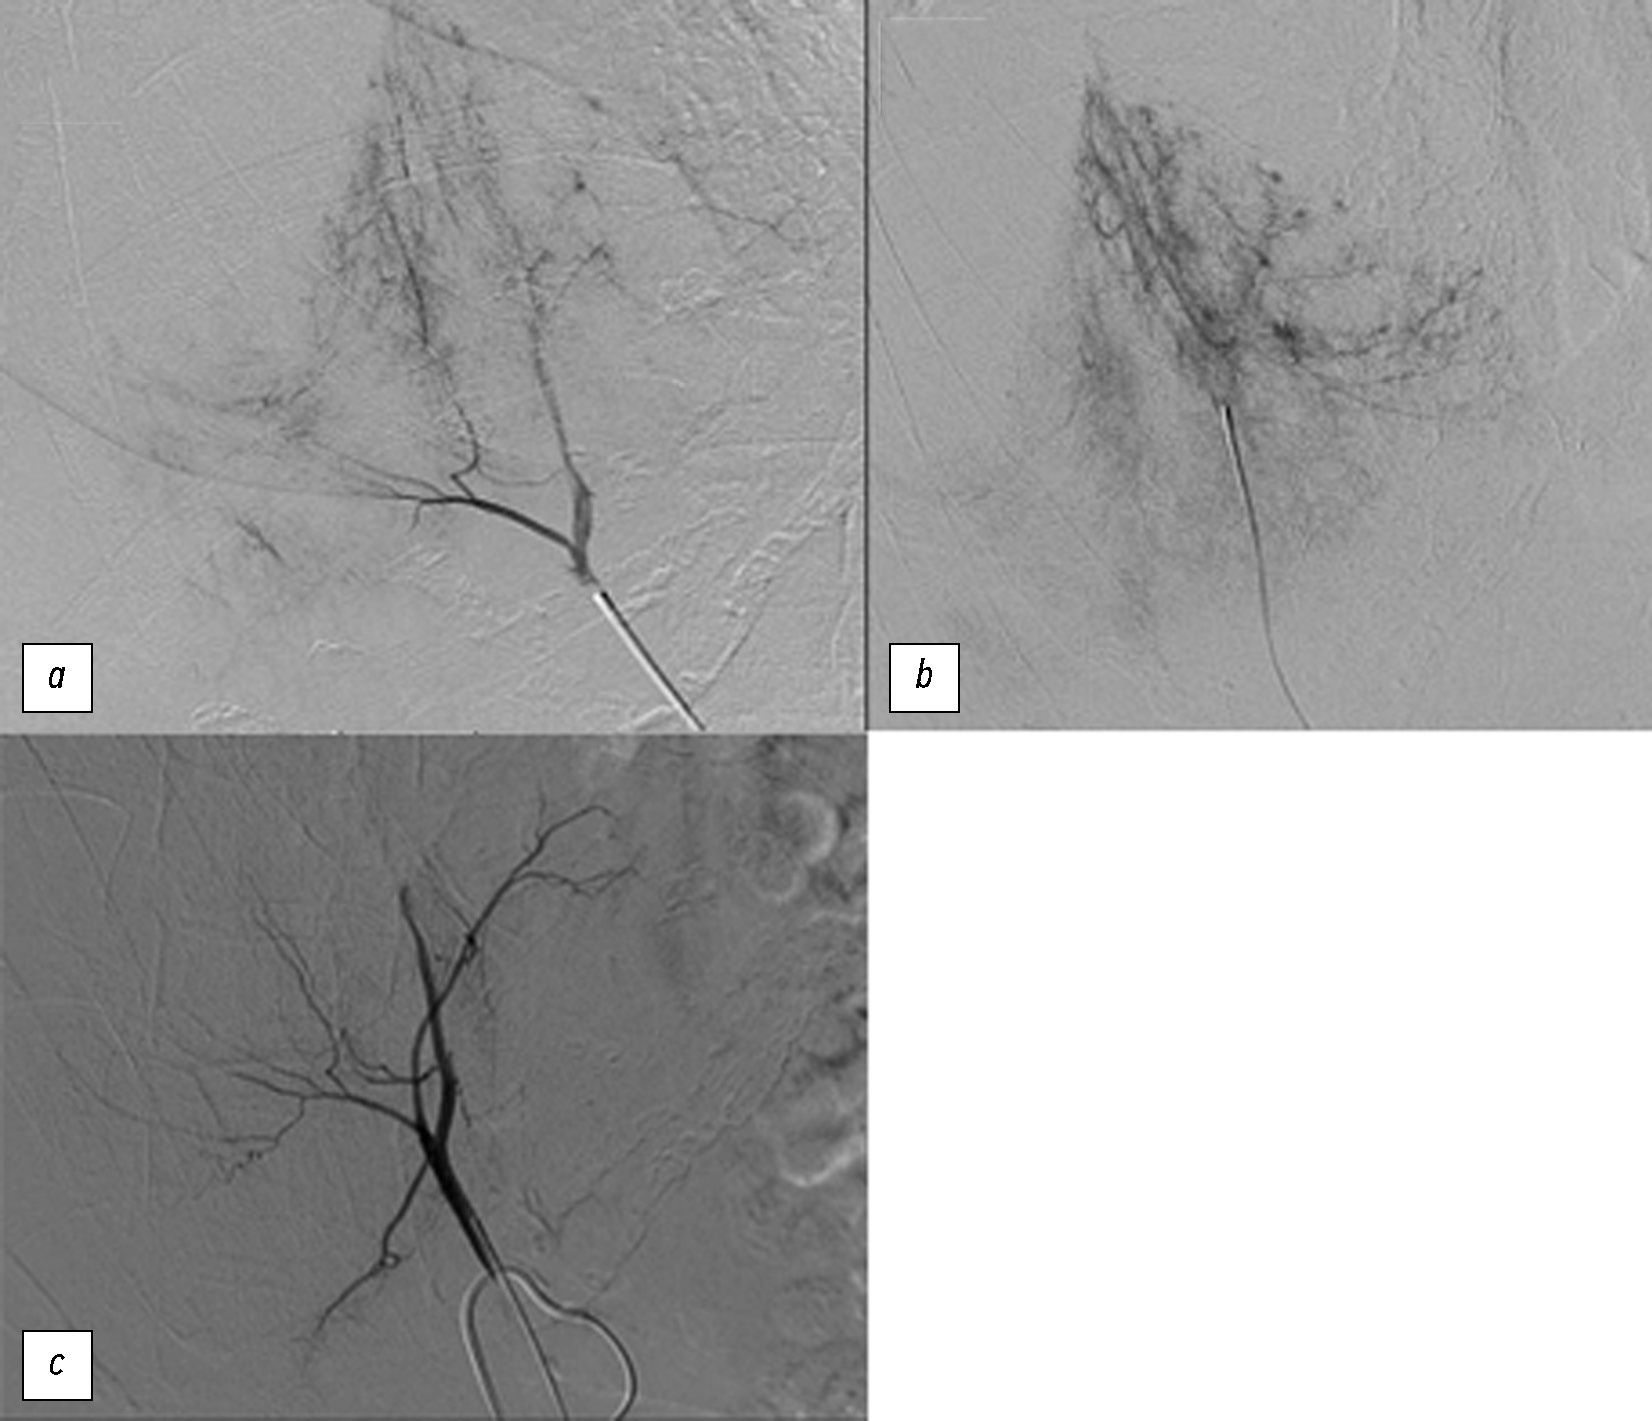

Учитывая тяжесть клинического состояния, пациентке сразу после рентгенологических исследований была проведена ангиоэмболизация, а также эмболизация точек незначительных утечек контрастного вещества, затрагивающих VII и VIII сегменты печени. Для их выявления в VII и VIII сегментах печени провели селективную катетеризацию чревного ствола и верхней брыжеечной артерии [8, 9].

Была проведена микрокатетеризация ранее упомянутых печёночных ветвей, и для их эмболизации было введено 2 мл микросфер (BEAD BLOCK диаметром 300–500 мкм) [10, 11] (рис. 4).

Рис. 4. Ангиография печени. a, b — по результатам первой артериографии в паренхиме печени наблюдалось несколько очагов артериального кровотечения, соответствующих VII и VIII сегментам печени; c — контроль после эмболизации с использованием 2 мл частиц на основе поливинилового спирта диаметром 300–500 мкм показал, что очаги кровотечения были полностью эмболизированы при заключительном осмотре.